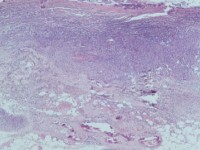

kleine en medium-size arteriën. De kalkafzettingen kunnen in een huidbiopt

worden gezien in en ook rond de vaten in de dermis en subcutis. Op

![Calciphylaxis cutis bij nierinsufficiëntie en secundaire hyperparathyreoïdie (click on photo to enlarge) [source: www.huidziekten.nl] Calciphylaxis cutis bij nierinsufficiëntie en secundaire hyperparathyreoïdie](../../../images/calciphylaxis-1z.jpg) |

![Calciphylaxis cutis bij nierinsufficiëntie en secundaire hyperparathyreoïdie (click on photo to enlarge) [source: www.huidziekten.nl] Calciphylaxis cutis bij nierinsufficiëntie en secundaire hyperparathyreoïdie](../../../images/calciphylaxis-2z.jpg) |

| calciphylaxis cutis |

calciphylaxis cutis |